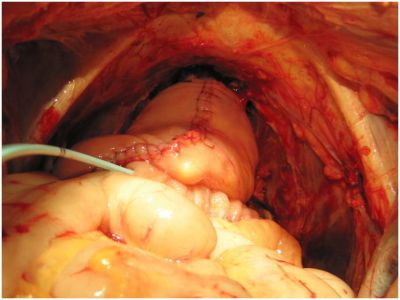

Пластическая реконструкция мочевого пузыря сегментом тонкой кишки (по меоду Штудера) после  цистэктомии по поводу рака.

Мочевой резервуар, анастомозированный с уретрой